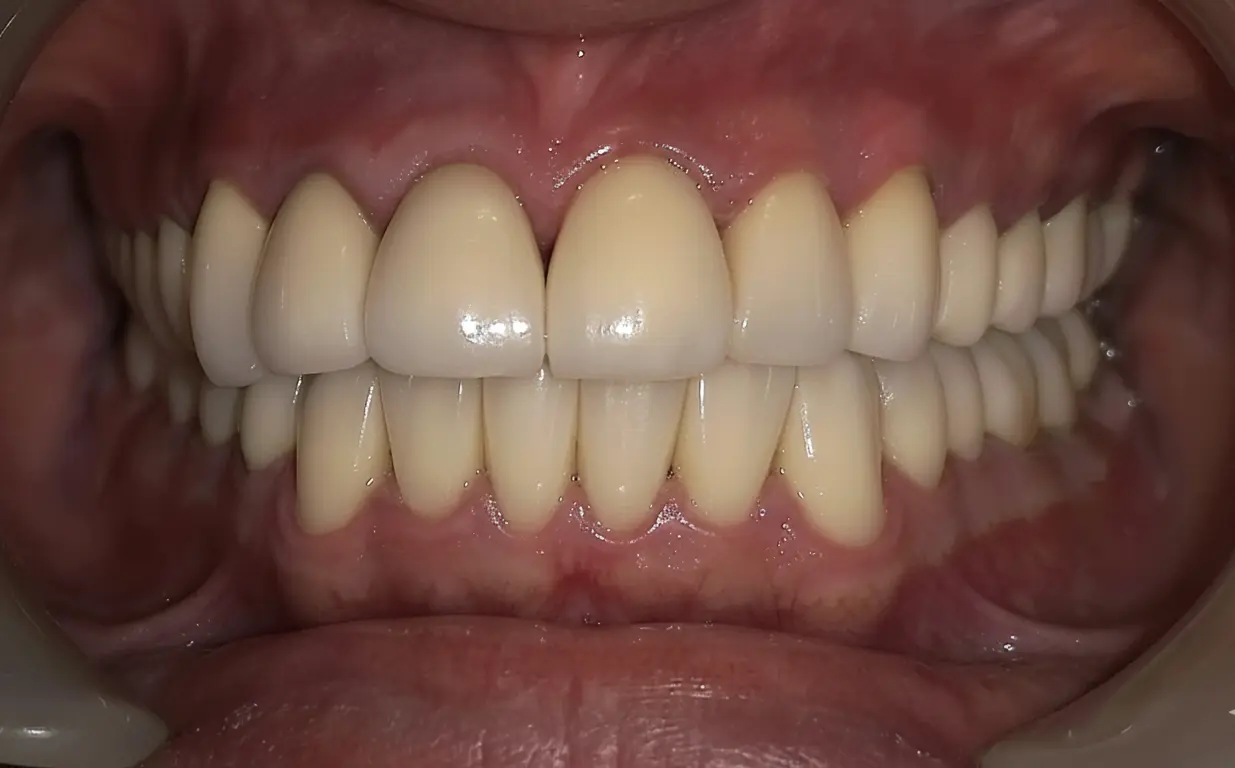

Final crowns after full mouth reconstruction

Final crowns restoring function and esthetics

After full mouth reconstruction

After: improved chewing comfort and balance